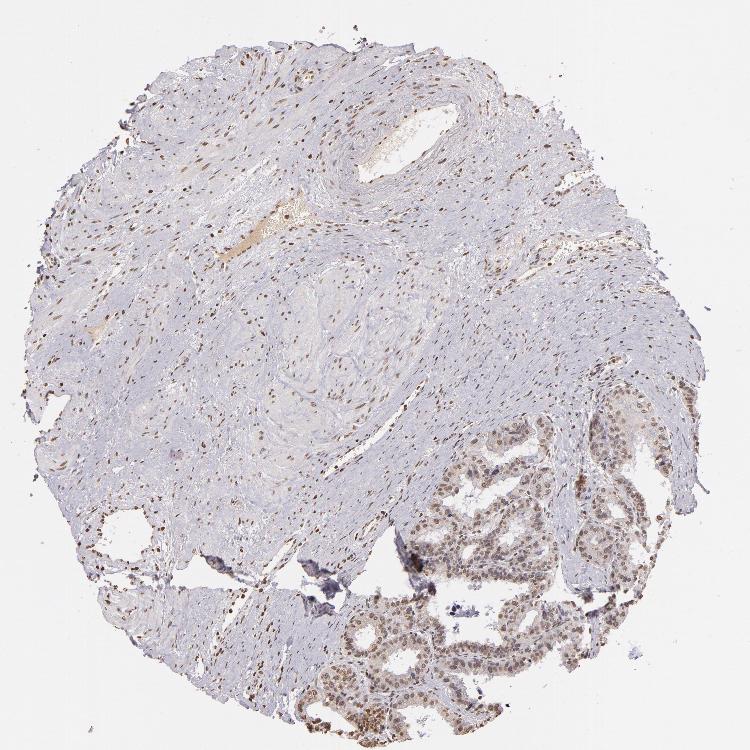

PROSTATE - Antibody stainingi

Antibody staining in the annotated cell types in the current human tissue is reported as not detected, low, medium, or high, based on conventional immunohistochemistry profiling in selected tissues. This score is based on the combination of the staining intensity and fraction of stained cells.

Each image is clickable and will lead to virtual microscopy that enables deeper exploration of all samples and also displays staining intensity scores, fraction scores and subcellular localization as well as patient and tissue information for each sample.

Antibody CAB002008Antibody CAB002009

Glandular cells Not detectedLow